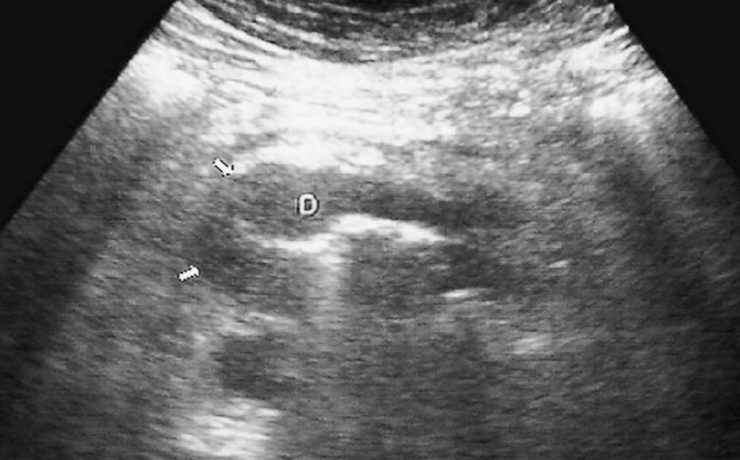

LA IMPORTANCIA DE LA ECOGRAFIA A LAS 11+0 A 13+6 SEMANAS DE EMBARAZO

Al principio, el ultrasonido en el primer trimestre se empezó a utilizar para medir la longitud cráneo-caudal del feto y estimar la edad gestacional, pero actualmente, además de eso, se evalúan varios detalles que permiten hacer una evaluación completa para identificar factores de riesgo que compliquen la gestación. Los objetivos